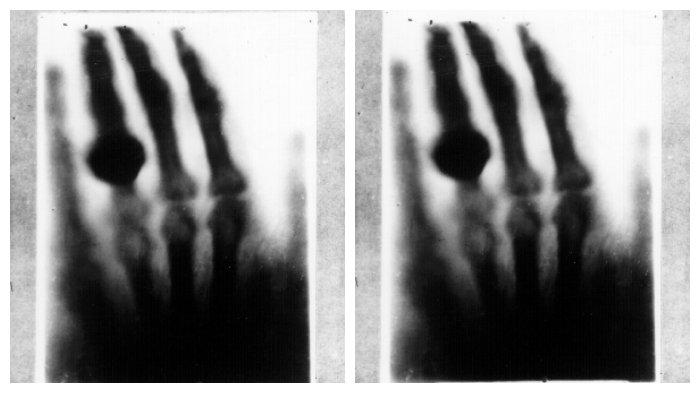

Foto Sinar X pertama dari tangan istri Wilhelm Conrad Rontgen

Dia juga menemukan bahwa jika tangannya diletakkan di antara tabung vakum bermuatan elektrik dan layar yang dilapisi barium platinocyanide, dia bisa melihat tulang tangannya.

Rontgen mengulangi percobaan ini bersama istrinya dan membuatnya ketakutan.